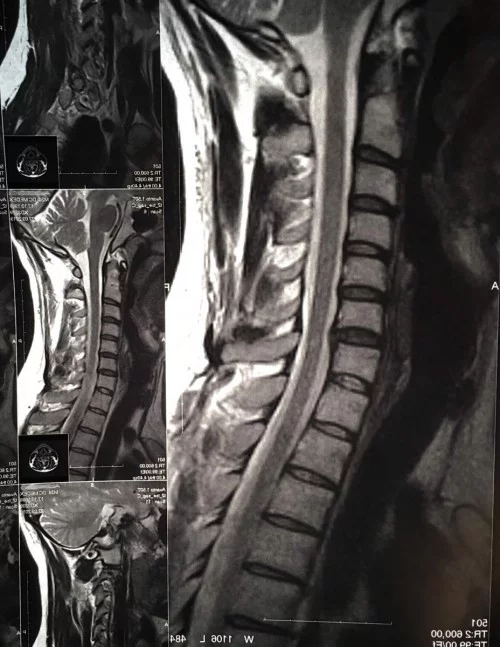

Причина грыжы -- излишний тонус мышц передней верхней части шеи (это только из того, что ясно по снимкам). В целом же вы описываете постоянный гипертонус постуральных мышц. Причины тому искать надо по телу (от черепа до крестца), снимки тут не помогут. Обратить внимание на прикус -- сам по себе тонус жевательной мускулатуры (после потери, объёмного ремонта нескольких зубов, например), очень даже делает такую картину

А можно при грыжах (С6-С7 медіанна екструзія 3мм з сублігаментозним каудальним поширенням до 5мм) шейного отдела использовать воротники такого плана?

Видно. Там боковой еще в др режиме неплохо было бы выложить.

вот оновили снимок на 1.5тл :клас: